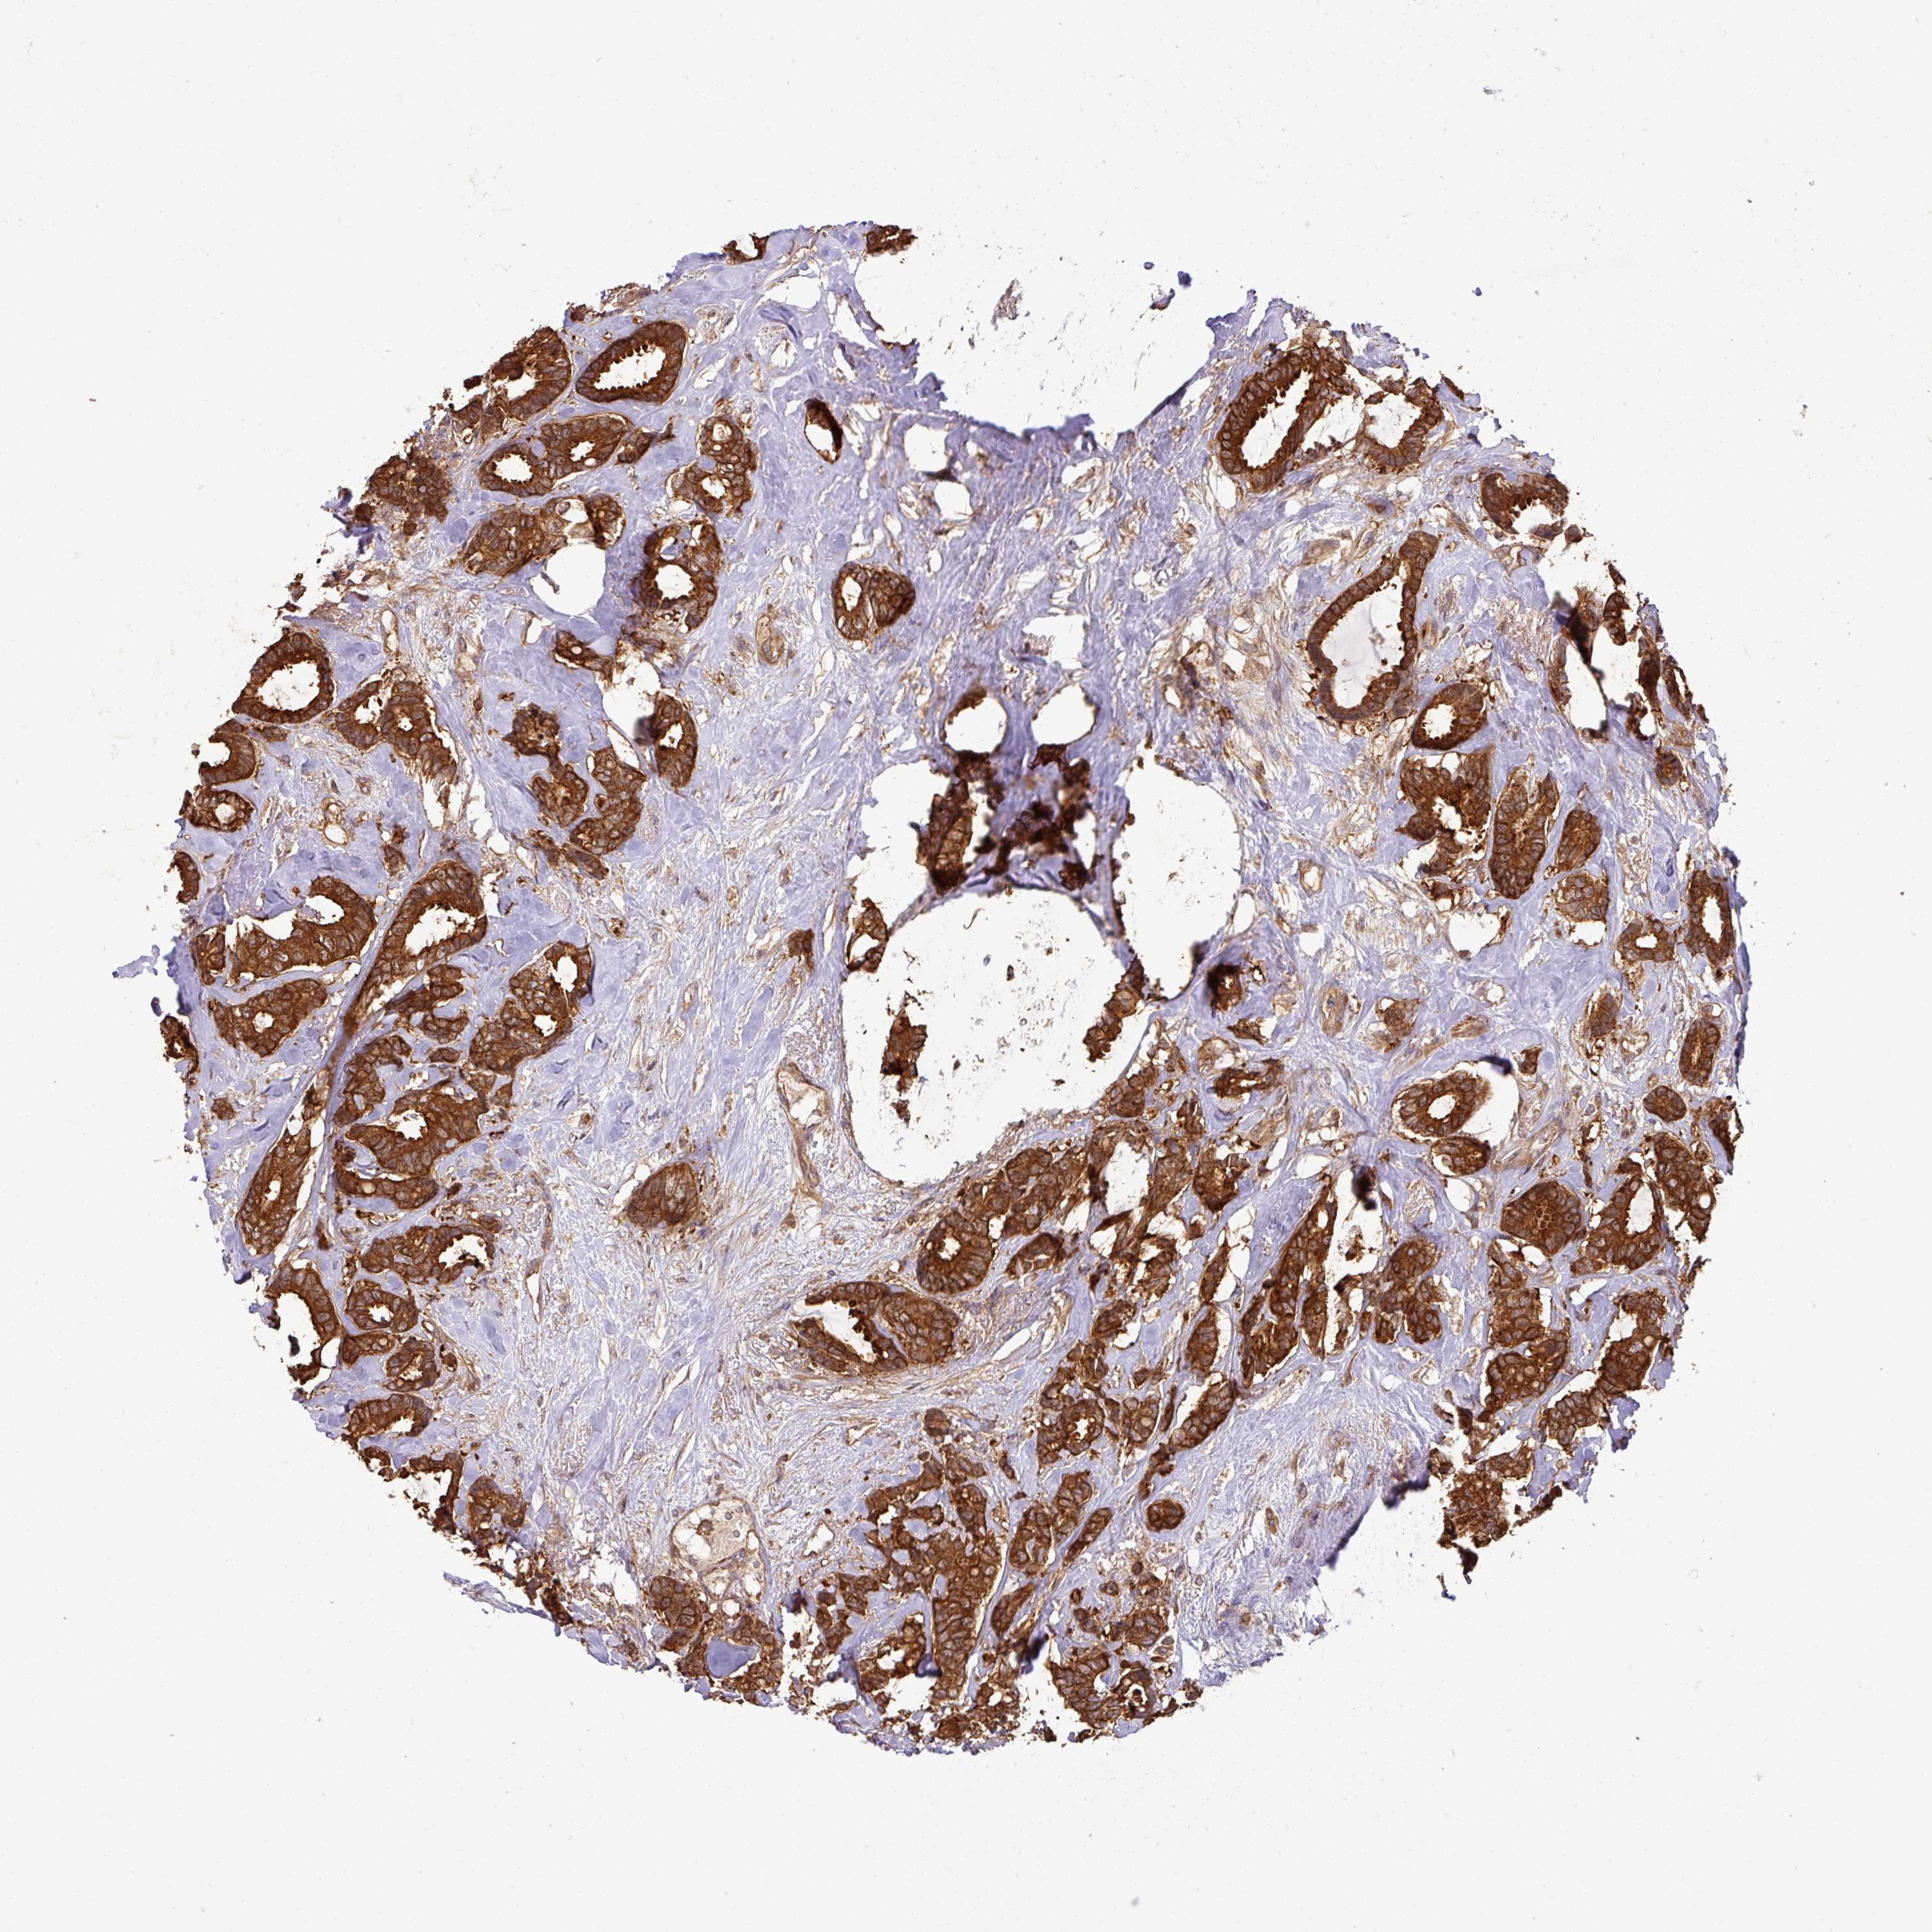

CANCER BREAST CANCER Show tissue menu

BRCA TCGA BRCA VALIDATION PROTEIN EXPRESSION

ANTIBODIES

AND

VALIDATION